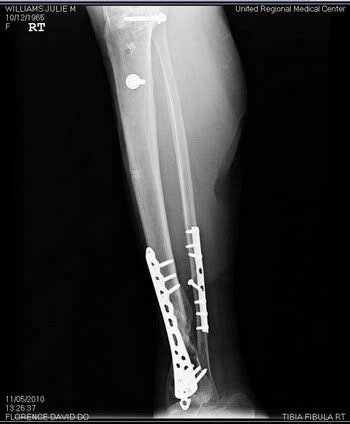

Most people don't understand why I am the way I am. I hope these x-rays give them a better idea of what I have to deal with every single day.

My right tibia (shin)